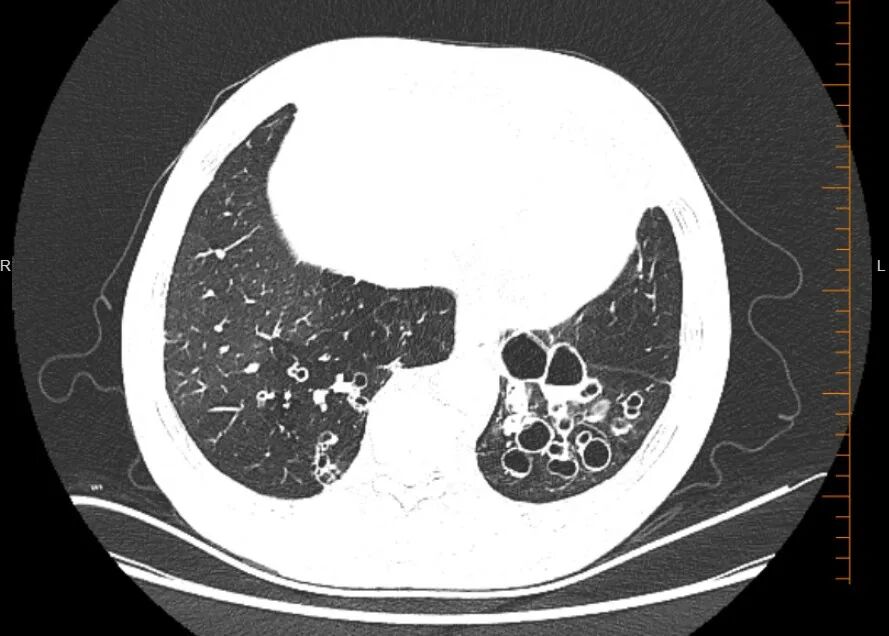

支气管扩张症是一种以咳嗽、咳痰和反复呼吸道感染等临床症状为特征的慢性炎症性肺病。该病症通过胸部CT扫描显示支气管扩张的影像学表现来确诊。病因涉及多种潜在因素,包括感染性疾病、自身免疫性疾病、过敏反应及遗传因素。支气管扩张症治疗的核心目标在于改善患者生活质量、缓解症状,并预防病情加重与疾病进展。